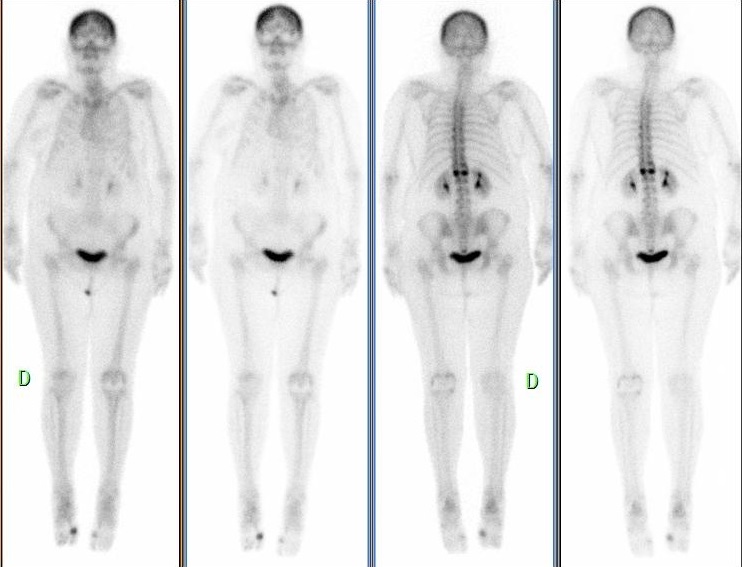

Ostéonécrose aseptique vertébrale

Rachialgie post traumatique (chute il y a 15j) avec sur la TDM des fractures vertébrales de T12 et L1.

tissulaire: foyer d’hyperémie se projetant en regard de L1.

Pas de foyer d’hyperémie en regard de T12.

osseux: hyperfixation intense de la partie postérieure du corps vertébral de L1 avec sur les données TDM un collapsus ischémique avec présence de gaz intra-vertébral.

Pas d’hyperfixation en regard de la fracture du plateau supérieur de T12.

Fracture récente du corps vertébral de L1 avec aspect d’ostéonécrose aseptique (maladie de Kümmel-Verneuil).

Fracture ancienne du plateau supérieur de T12.